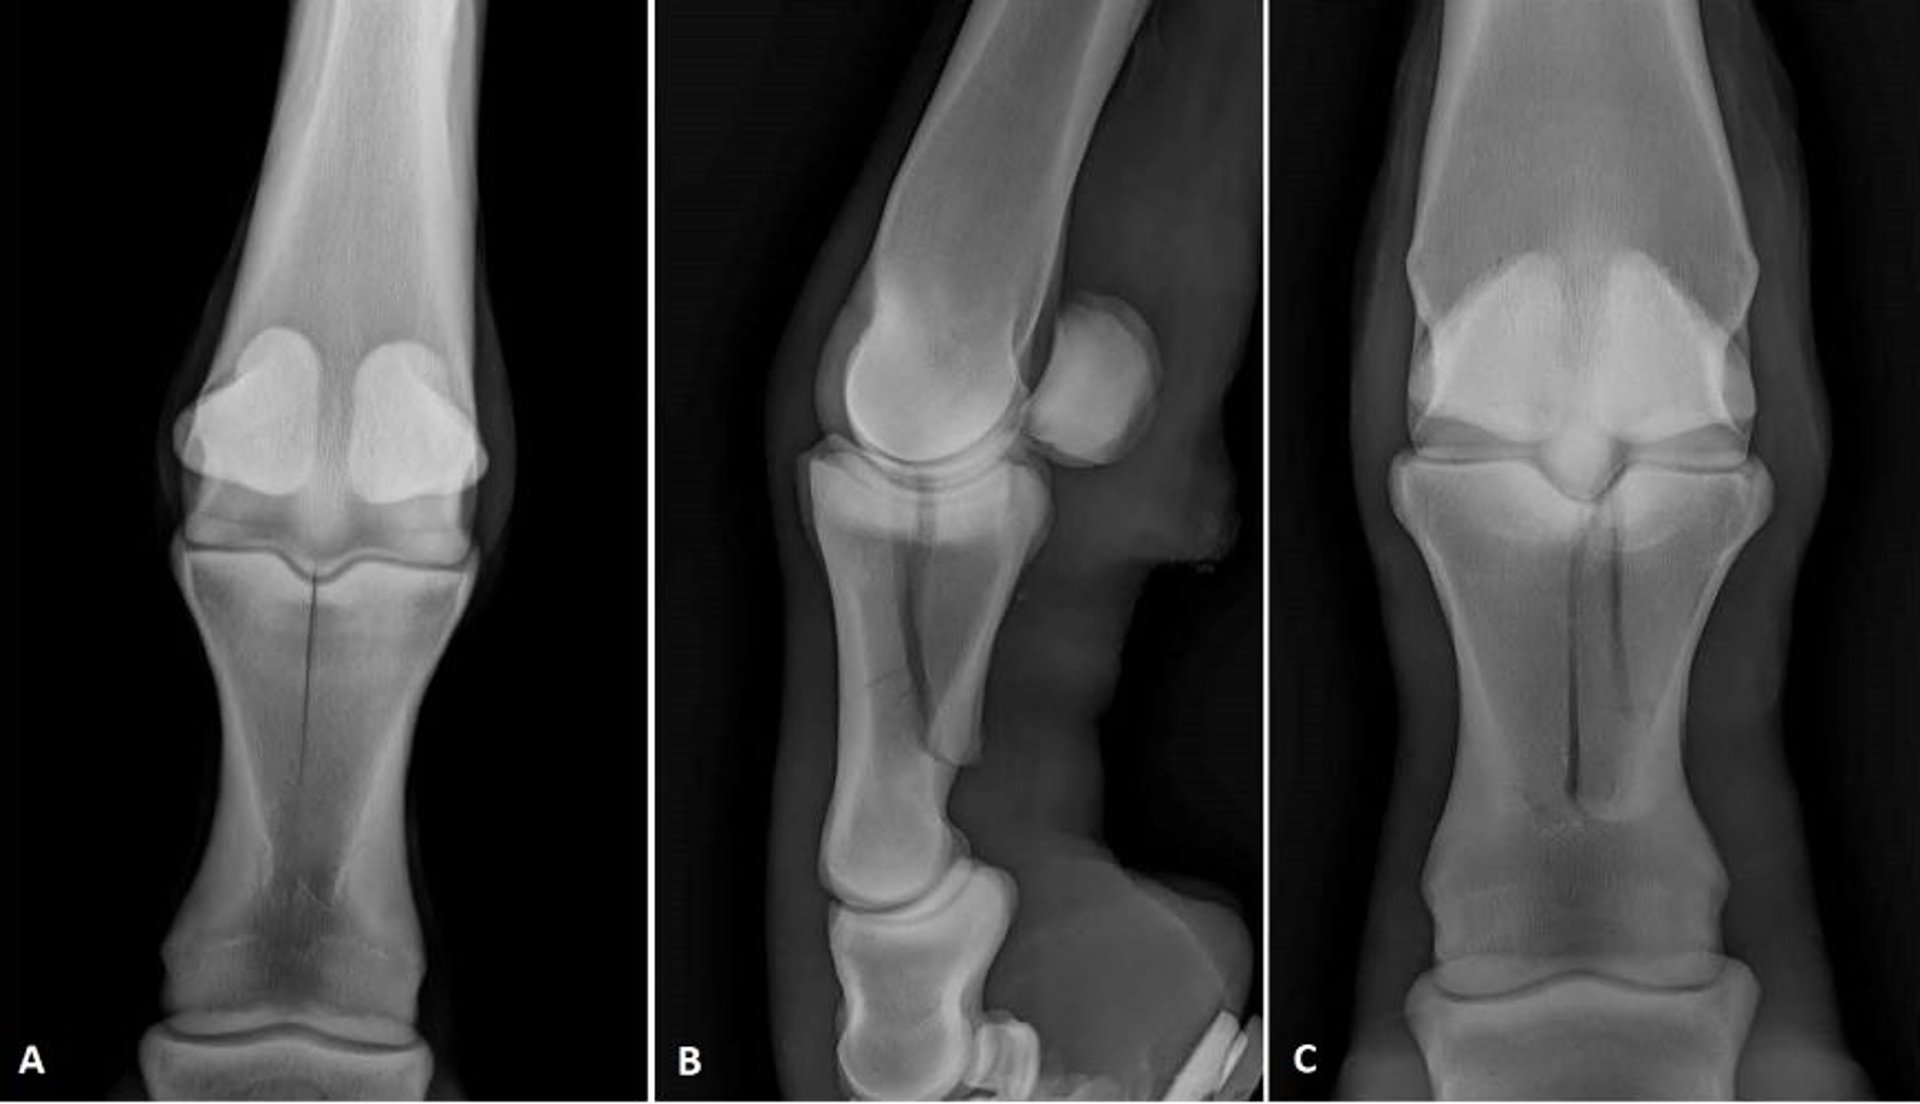

Radiografías de fracturas de la P1 en caballos

Imágenes radiográficas que muestran dos configuraciones diferentes de fracturas de la primera falange en caballos. (A) Vista dorsopalmar de una fractura sagital incompleta. (B) Vista lateral y (C) vista dorsopalmar de una fractura complicada.

Cortesía del Dr. Matthew T. Brokken.